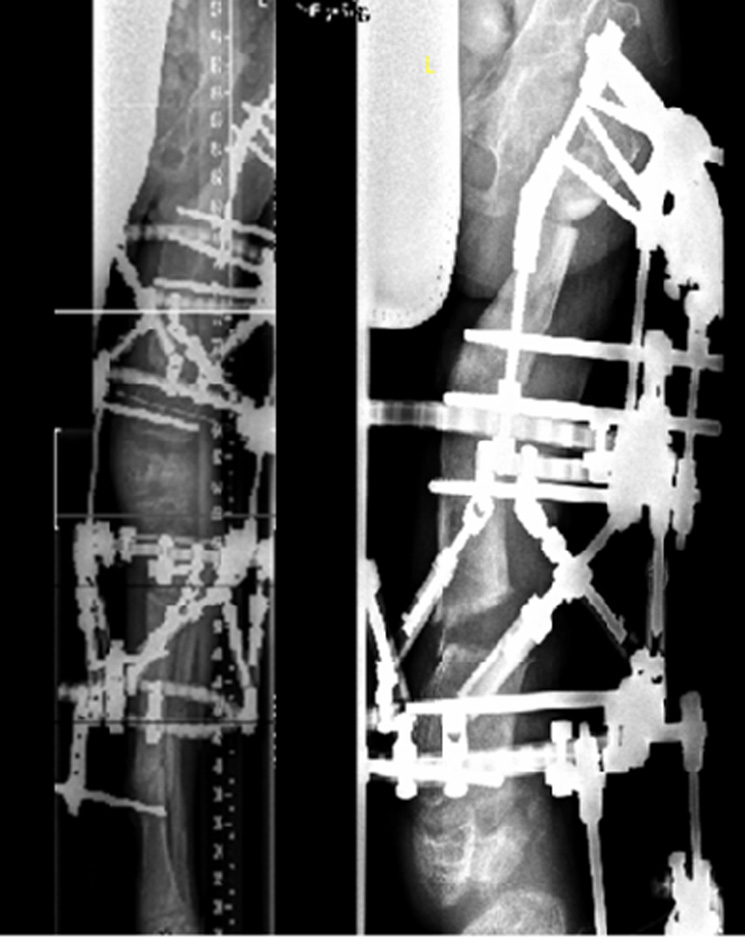

Figure 5

After distal femoral and proximal tibial osteotomy, the severe varus deformity was corrected by gradual distraction using the Taylor Spatial Frame™.

Figure 6

After consolidation and removal of the frame, a prophylactic nailing of the right femur and tibia was performed to obtain the correction.